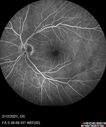

Branch Retinal Vein Occlusion with Venous Macroaneurysm (collateral)280 views66 year old female Did not notice vision loss in the right eye. The right eye has been a little worse than the left but now is much worse. Picked up during annual eye examination. VA had been 20/20 in 5 years ago.

History of brain and spinal cord radiation 1986 for T-cell lymphoma. Now with breast cancer, ablation for tachycardia, HTN

VA OD 6/200, OS 20/32Oct 16, 2021